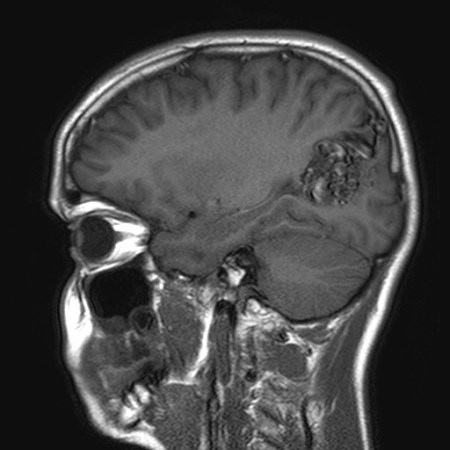

Unruptured left parieto-occipital arteriovenous malformation (sagittal T1-weighted magnetic resonance imaging scan)

From the collection of Mr R. J. Edwards; used with permission